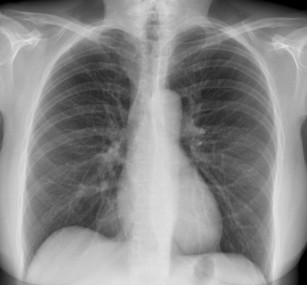

Oasele absorb cel mai mult radiatiile de aceea ele apar pe radiografie alb intens. O radiografie toracica ofera imagini ale inimii plamanilor cailor respiratorii vaselor de sange coloane. Daca la unele persoane aceste opacitati sunt mai mari insa cu contur net nu trebuie sa le socotim ca patologice intrucat opacitatile hilare pot varia ca marime de la un individ la altul. Opacitatile hilare longitudinale si circulare sunt imagini normale ce se gasesc la toti oamenii sanatosi.

Inima diafragmul si celelalte tesuturi din torace absorb si ele radiatiile realizand diferite nuante de alb. Cancerul la plamani pulmonar simptome. Plamanii care sunt plini cu aer vor aparea pe radiografie in mod normal ca niste umbre intunecate. Multa stima domnule profesor m ati diagnosticat acum 25 de ani cu bpoc forma severa m ati invatat sa ma tratez dar mai ales sa raman activ nnu am fumat niciodata acum am 46 de ani si conduc un liceu va rog ajutati ma sa i ajut pe liceeni sa se lase de fumat prin metode si materiale moderne de informare cu impact mare asupra lor pliante filme povestiri adevarate astept o veste la e.